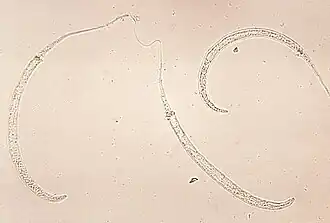

Larven von Dracunculus medinensis, dem Medinawurm

Dracunculus (lateinisch dracunculus kleine Schlange, Verkleinerungsform von draco Drache) ist eine Gattung von Fadenwürmern (Nematoden), deren Arten als Parasiten in Gewebe und Körperhöhlen von Reptilien und Säugetieren einschließlich des Menschen vorkommen.